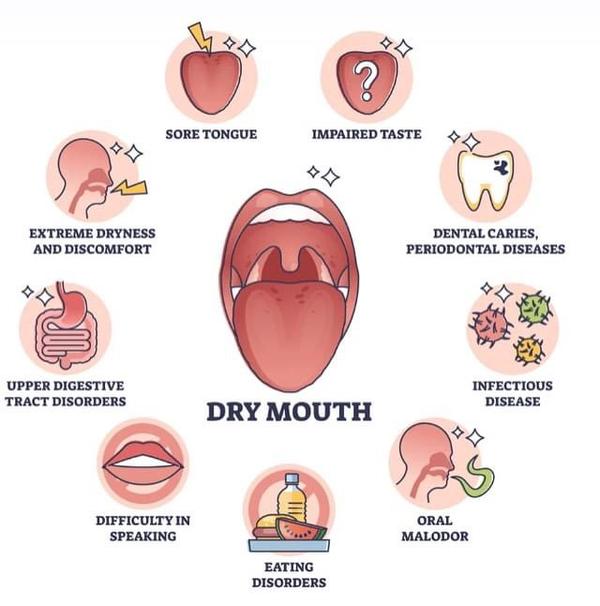

Top dentist in Adambakkam | Dry Mouth: Causes and ...

View Details